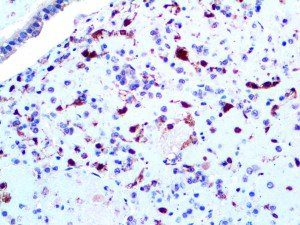

It is the ICU physician who is most likely to witness one of the deadliest manifestations of the abnormal immunological response, the cytokine storm syndrome (CSS). This response is also referred to by some as the cytokine release syndrome (CRS). CSS is characterized by continuous activation and expansion of macrophage and lymphocyte populations, which secrete large amounts of cytokines, causing the cytokine storm. This massive cytokine release is akin to hemophagocytic lymphohistiocytosis (HLH) disease, a syndrome characterized by initial unchecked and persistent activation of cytotoxic T lymphocytes and NK cells.

Clinical and laboratory manifestations of HLH include fever, enlarged liver and/or spleen, neurologic dysfunction, coagulopathy, liver dysfunction, cytopenias (i.e., low levels of erythrocytes, leukocytes, and/or platelets), hypertriglyceridemia, hyperferritinemia, hemophagocytosis, and eventually diminished NK cell activity as the immune system becomes progressively paralyzed. HLH can be familial (primary HLH) or secondary to another disease process (sHLH), such as rheumatic disease, in which it is referred to as macrophage activation syndrome (MAS, characterized by elevated ferritin).